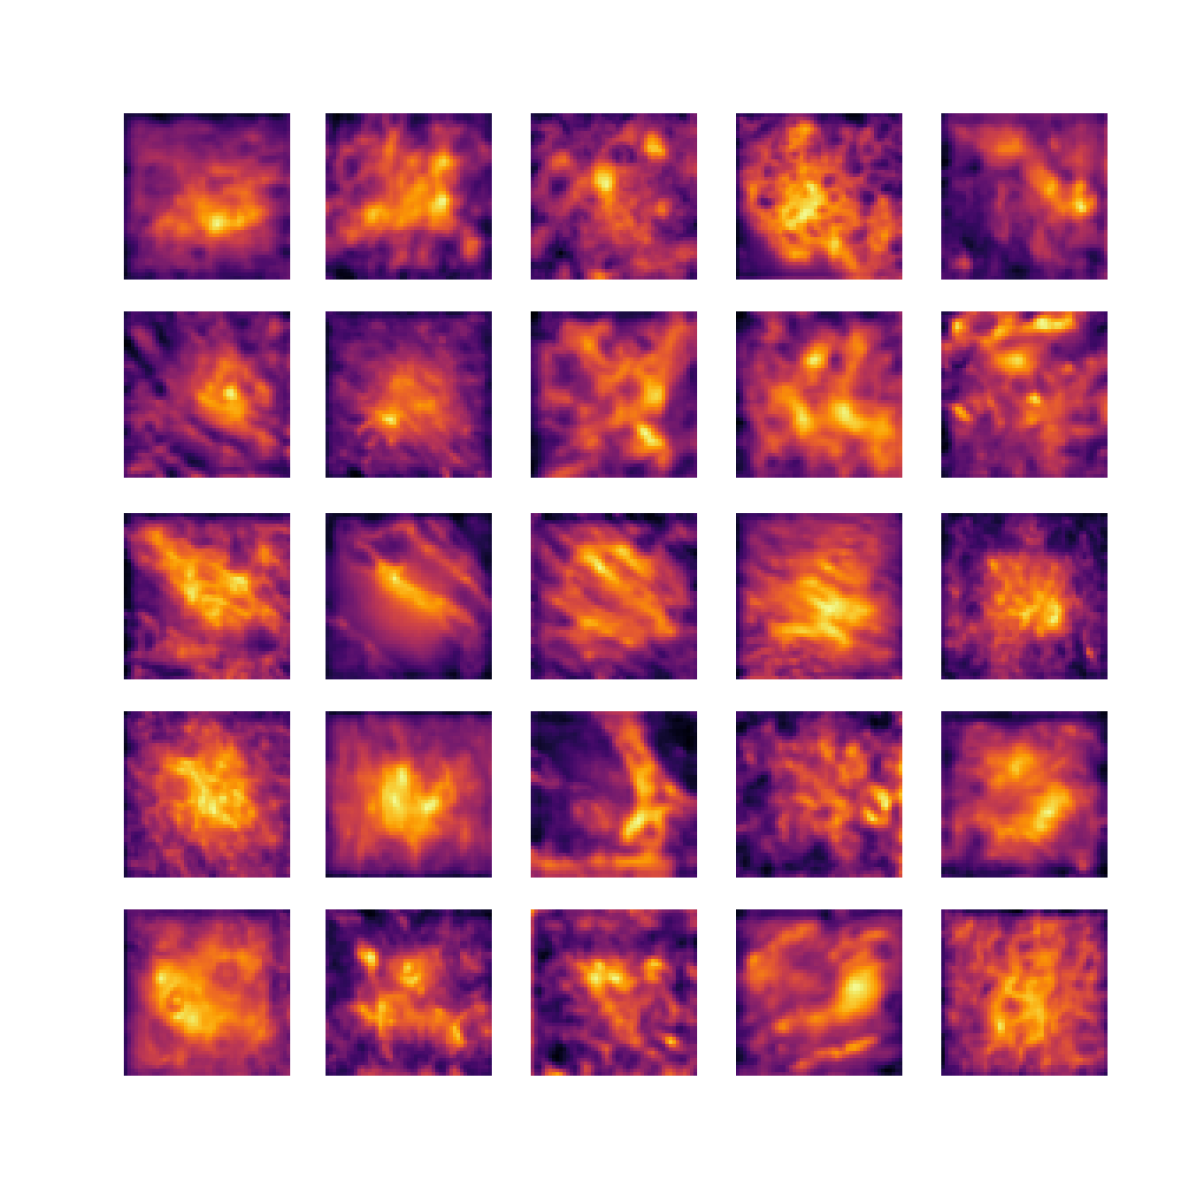

We also analyse the activation maps for each model using GradCAM as described in section S3. This offers more insight into the areas of the image which are contributing most heavily to the models’ representations. In Figure 4(b) we present some representative examples, however, a larger selection which was chosen at random is presented in Figures S10 to S25. The larger selection makes it easier to see the emergent patterns, including that privileged Siamese models tend to mainly identify features which are strongly present in both inputs, while unprivileged Siamese models tend to learn more diffuse features that are not specific to one cell phenotype or image region. TriDeNT ♆ incorporates both sets of features, learning both features specific to the privileged data and more the general features associated with unprivileged Siamese networks.

We can see in Figure 4(b) panel A that for ERG, the privileged Siamese model focuses almost exclusively on any nuclei which could be endothelial cells. As there are very few endothelial cells in the dataset, it could be an effective strategy to identify anything that could potentially be an endothelial cell to minimise the difference between the representations of the H&E model and the IF mask model. In the corresponding unprivileged Siamese image, we see that the model identifies some of these nuclei, albeit less strongly, but also focuses heavily on the other tissue and even the background, while strongly fixating on two spots of debris in the center of the image. This model has less ‘incentive’ to learn the weak features related to endothelial cells as these occur rarely and are not easy to detect, while more generic strong features such as the presence of connective tissue and the prevalence of background are more common and predictable from augmented images. We see that TriDeNT ♆ combines these two feature sets, strongly identifying nuclei while also identifying the connective tissue.

In panel C we see a similar pattern, with the privileged Siamese model fixating solely on the nuclei, while the TriDeNT ♆ model takes a more balanced approach. The unprivileged Siamese model appears to focus on a single cluster of nuclei while neglecting others, and similarly identifies an area of fibroblasts with its distinctive pattern but does not others.

In contrast to panels A and C which represent models with poor privileged Siamese results, panels B and D represent models whose privileged Siamese results were comparable to both TriDeNT ♆ and even the supervised baseline. It is therefore interesting to note that there are far more similarities between the privileged Siamese and TriDeNT ♆ models in both cases. Particularly in panel B, TriDeNT ♆ and the privileged Siamese model return virtually identical heatmaps, with both strongly identifying epithelial nuclei and neglecting the same areas of connective tissue. The unprivileged model in this case appears to focus solely on the centre of the image, giving a significantly different heatmap to the other panels.

Panel D again shows the previous pattern, with the privileged Siamese model identifying the features strongly present in the privileged data – fibroblasts – while neglecting the nuclei present. TriDeNT ♆ also strongly identifies the connective tissue, but, unlike the privileged Siamese model, does not completely neglect the nuclei. The unprivileged Siamese model primarily identifies background, and does not appear to identify the nuclei in this example.